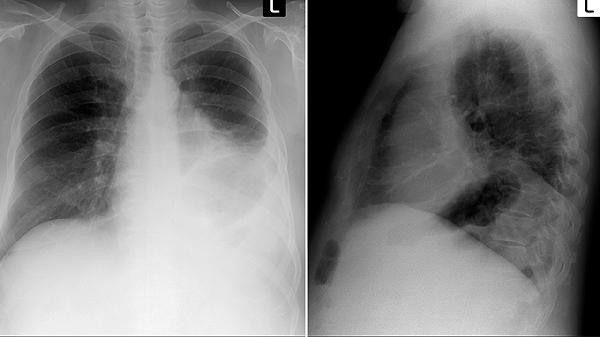

方中夏枯草、山慈菇等具有软化消散结节的作用,适用于8毫米以下的良性肺结节,能抑制结节增长。对于恶性肿瘤配合放化疗使用时可减轻病灶周围水肿。需定期复查胸部CT观察结节变化。